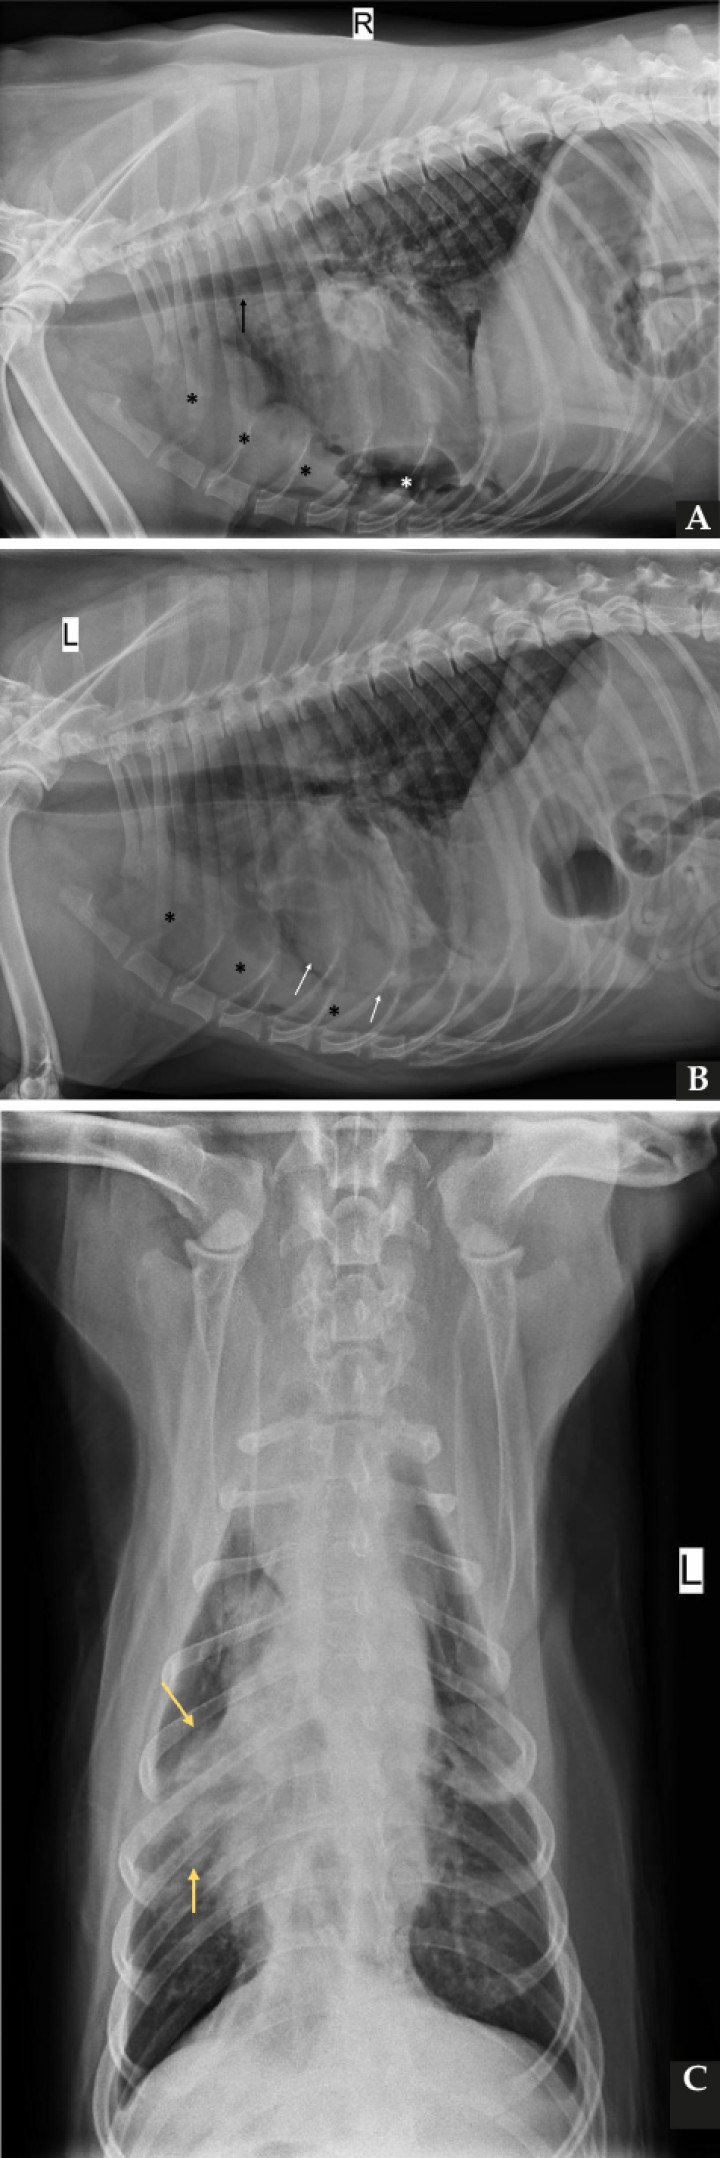

Tras la estabilización del paciente se realizaron tres proyecciones radiográficas del tórax (Fig. 1).

<p>Radiografías de la cavidad torácica de un perro mestizo de 9 años. (<strong>A</strong>) Proyección lateral derecha. (<strong>B</strong>) Proyección lateral izquierda. (<strong>C</strong>) Proyección ventrodorsal.</p>

Radiografías de la cavidad torácica de un perro mestizo de 9 años. (A) Proyección lateral derecha. (B) Proyección lateral izquierda. (C) Proyección ventrodorsal.

Se observa la presencia de una silueta de opacidad líquido/tejido blando, márgenes irregulares y poco definidos, que provoca un aumento marcado de la anchura del mediastino craneal (>2 veces el ancho de la columna vertebral) en la proyección ventrodorsal (VD), localizada en el aspecto ventral del mediastino craneal (Fig. 2). Dicha lesión produce un moderado efecto masa y desplaza la tráquea en sentido dorsal en las proyecciones laterales, así como la silueta cardiaca y los lóbulos pulmonares craneales en sentido caudodorsal compatible con una masa mediastínica.

<p>Mismas imágenes que en Figura 1. Se observa una silueta de opacidad líquido/tejido blando (asteriscos negros) en el mediastino craneoventral, produciendo elevación dorsal de la tráquea (flecha negra) y desplazamiento en sentido caudodorsal de la silueta cardiaca (flechas blancas) (<strong>A</strong> y <strong>B</strong>). Además, se aprecia atelectasia del lóbulo medio derecho (flechas amarillas) (<strong>C</strong>) y pequeñas estructuras de opacidad gas (asterisco blanco) (<strong>A</strong>).</p>

Mismas imágenes que en Figura 1. Se observa una silueta de opacidad líquido/tejido blando (asteriscos negros) en el mediastino craneoventral, produciendo elevación dorsal de la tráquea (flecha negra) y desplazamiento en sentido caudodorsal de la silueta cardiaca (flechas blancas) (A y B). Además, se aprecia atelectasia del lóbulo medio derecho (flechas amarillas) (C) y pequeñas estructuras de opacidad gas (asterisco blanco) (A).

Los lóbulos pulmonares caudales presentan los bordes redondeados debido al derrame pleural remanente tras el drenaje (Fig. 2). Además, se visualizan varias estructuras de densidad gas en el aspecto caudoventral del tórax, superpuesto parcialmente con la silueta cardiaca. Dicho gas puede ser de origen mediastínico o pleural, posiblemente yatrogénico. Se aprecia un moderado patrón bronco-intersticial generalizado con atelectasia del lóbulo medio derecho, sin evidencia de nódulos o masas pulmonares. La silueta cardiaca no presenta alteraciones reseñables (índice vertebral cardiaco: 10.2).

El resto de estructuras intra y extratorácicas visibles no muestran alteraciones evidentes.